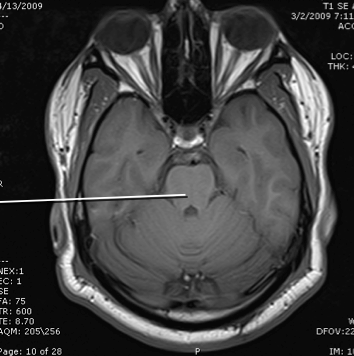

crus cereberi

hypothalamus

cerebral aqueduct

cerebellum